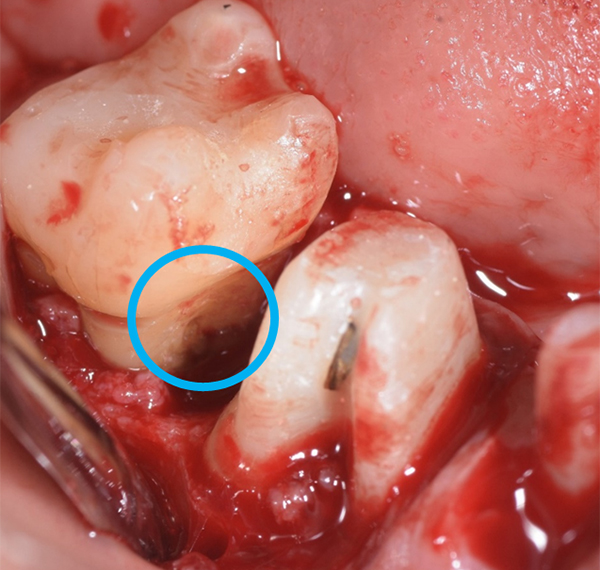

軽度〜中程度レベルの歯周炎であれば、ここで改善が見られますが、中程度以上の歯周炎の場合は、その後に歯周外科処置を行うことが多いです。なぜなら、歯周ポケットが5mm以上ある部位にSRPを行っても多くの歯石の取り残しがあるという報告があるため、深い歯周ポケットを有する患者さんに対しては歯周外科処置を行います。歯周外科処置で一般的な術式は歯肉剥離掻爬術です。痛く無いように麻酔(局所麻酔)をした後、歯肉をメスで切り(切開)、切った歯肉を骨から剥がし(剥離)、歯の根に付着した歯石、歯槽骨の形態などが直接見える状態で、歯石や感染物の除去を行います。その際必要であれば、その後に患者さん自身で清掃がしやすいように骨の形態を整える歯槽骨整形も行います。最後に切った部分を縫って(縫合)処置を終わります。

歯周組織再生療法といい、先に記しました通り、GTR法、エムドゲインを使用した方法、リグロスを使用した方法といくつかあります。GTR(Guided Tissue Regeneration)法とは、歯周外科処置と同様に歯肉をメスで切り(切開)、切った歯肉を骨から剥がし(剥離)、歯の根に付着した歯石、歯槽骨の形態などが直接見える状態で、歯石や感染物の除去を行います。その後、骨が吸収して失われた部分にこのバリア膜で覆い縫って(縫合)処置を終わります。バリア膜で覆うことで、歯肉などの軟組織が骨の中へ直接入り込むことを防ぎ、新しい血管が新生され、歯周組織の再生を促します。治療後およそ6ヶ月待ちます。

エムドゲインは、エナメルマトリックスという幼若豚の歯の組織から抽出したタンパク質です。これも歯周外科処置と同様に進め、歯石や感染物の除去を行い歯根面を徹底的に綺麗に清掃した後、リン酸などで歯根を処理し、歯根面へエムドゲインを塗布し縫って(縫合)処置を終わります。

*エムドゲインゲル溶液の塗布